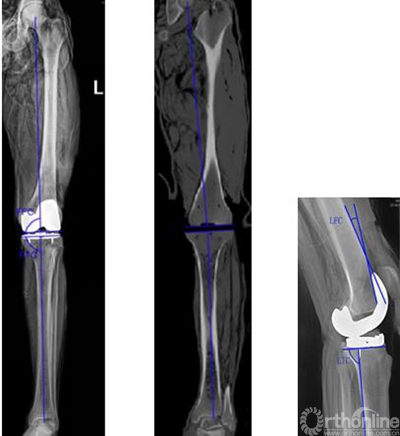

3.个性化导航模板在人工全膝关节置换中的实验研究

MR具有无辐射、无骨伪影、无损伤、高对比度、高分辨率等优点,在膝关节三维重建中较 CT 具有明显优势。我们基于MR数据,完成对髋-膝-踝骨性结构和关节软骨的三维重建和对股骨、胫骨机械轴线的测量,连接股骨头中心和膝关节中心获取股骨机械轴线,连接胫骨平台中心和踝关节中心获取胫骨机械轴线。

在Imageware13.0软件中建立局部三维坐标系,确定行股骨远端截骨的导航定位针孔所在的平面,再根据截骨模块两侧对称的固定针孔间的距离,垂直于确定的导航定位针孔所在的平面进行平行点云截面操作,通过点云拟合操作创建出两条直线,获得股骨远端截骨导航定位孔的位置(图11)。在Imageware13.0中基于股骨机械轴线及股骨外科髁上轴,建立局部参考坐标系,得到模块两条固定针进针的中心直线,即为导航定位孔方向(图12)。按照在Geomagic11.0中确定的胫骨截骨参照点及对截骨模板的测量,确定胫骨截骨导航定位针孔所在平面(图13)。调整该平面后倾角度,获得胫骨近端导航模板定位孔(图14)。根据整个下肢髋-膝-踝关节MRI数据建立股骨与胫骨机械轴线,按照实际膝关节的表面解剖形态设计模板的贴合面,确定导航管的位置与方向,从而设计出股骨、胫骨截骨定位的个体化导航模板,进行模拟截骨(图15)。

表一

研究表明,膝关节导航模板具有很高的股骨远端和胫骨近端截骨精确性和假体旋转轴线定位的准确性,为TKA提供了一种新的辅助方法。能够获取准确的下肢机械轴线、股骨远端假体旋转轴线、假体位置,同时也有效的减少了术后并发症,近期临床效果值得肯定。